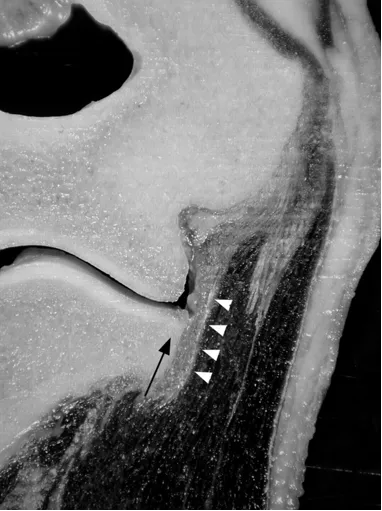

滑膜皱襞

后外侧滑膜皱襞,是关节滑膜增生折叠形成的结构,过度增生或损伤时可能引发关节不适。

(a)33 岁女性受试者的矢状位 T2 加权磁共振成像,以及(b)对应的示意图,清晰显示出后外侧滑膜皱襞的前后径(白色箭头所示)与头尾径(黑色箭头所示)。图中 AM 代表肘肌。

(c)与图 a 相同的磁共振影像,以及(d)对应的示意图,显示出肱骨小头的假性缺损(箭头所示),及其与后外侧滑膜皱襞的密切关联。图中 AM 代表肘肌。